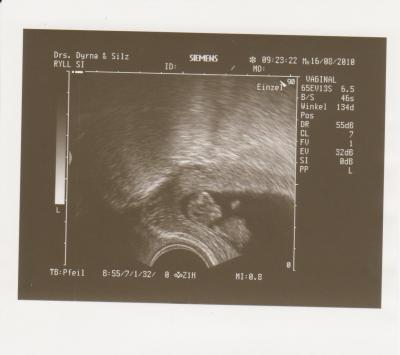

So ein Prachtkind. Und ich konnte sehen wie es mit seinen kleinen Ärmchen gezappelt hat, herrlich.

Leider hat er mir nicht gesagt wie groß es nun ist und auf dem Bild steht es leider auch nicht, aber er hat mich um 3 Tage vorgestuft, auf 10+6, d.h. ich bin ab morgen schon in der 12.SSW

So jetzt seht euch mal mein wunderbares Kind an

Huiii, da ist ja schon ein richtiges kleines Profil zu erkennen! Toll!

In echt ist das Gesichts-Profil richtig scharf zu sehen :-) hier ist das ja leider immer so verpixelt. Mein Mann hat auch sofort das gesagt was ich dachte, das die Nase voll vom papa kommt :-)